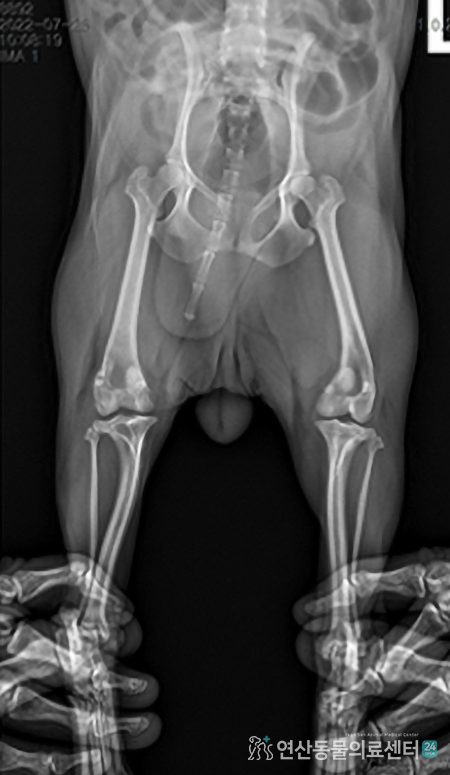

• 허혈성 괴사증 이미지

허혈성 괴사 대퇴골두제거 + 슬개골

대퇴 골두 허혈성 괴사증, 수술 후 근육 배열의 변화를

고려해 슬개골의 안전성을 지켜낸 특이케이스